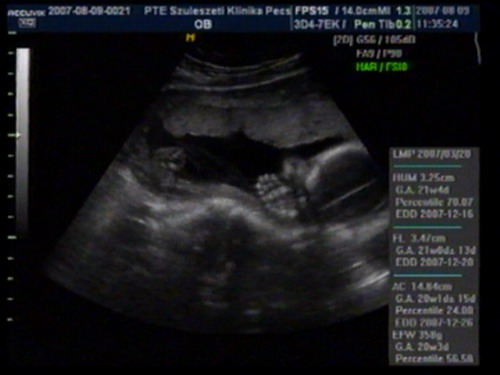

szedtünk le a videoról képet: Kép